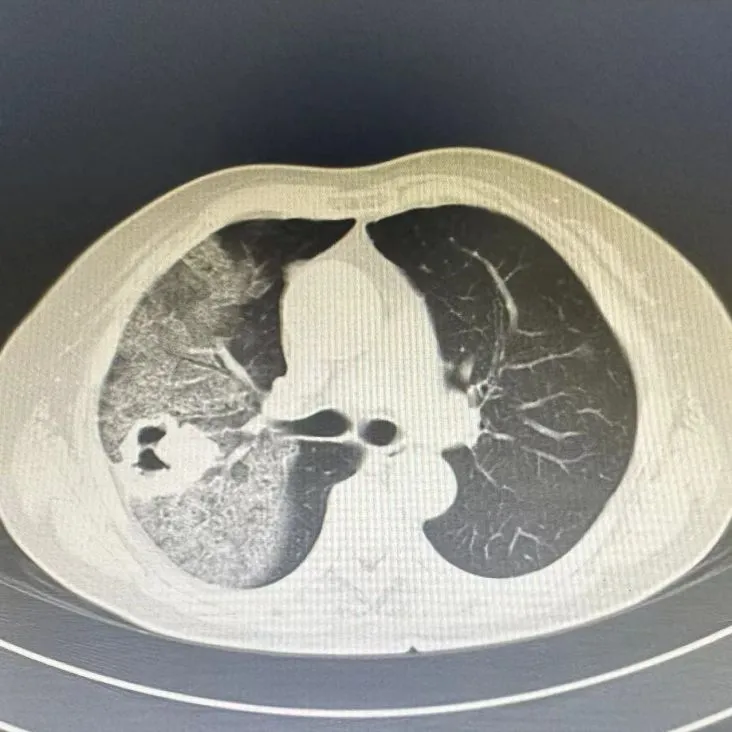

3个多月前,住在外地的患者S奶奶(76岁)在拔牙后开始出现痰中带血,起初量很少,S奶奶认为是拔牙所致,未予重视。大约十天后,咯血开始增多,每天8-10口暗红血痰。S奶奶和家人发觉情况不对,赶紧入住当地医院,经过一段时间的输液治疗后,病情并没有得到改善,仍然持续咯血。于是做胸部CT检查,发现右上肺大面积出血影,其中还夹杂着一个高密度团块影,有空洞形成、分叶状,高度怀疑肺部恶性肿瘤合并出血。焦急的S奶奶和家人慕名来到了朝阳医院呼吸与危重症医学科(石景山院区)(以下简称呼吸科)。S奶奶住院时已经在持续咯鲜血,当日咯血量高达500ml,血红蛋白80g/L,已属于中度贫血。呼吸科主任医师张黎明和王晶团队判断患者的病情紧急且危重,于是立即胸外科(石景山院区)主任医师张文谦会诊,经过充分讨论,两个科室的医疗团队很快达成一致:患者右肺上叶肿瘤合并大咯血,内科治疗已无法有效控制,急诊外科手术是救治患者唯一的希望。

在手术室、麻醉科和输血科等相关科室的全力配合下,急诊手术迅速开展。由于肺内大量出血,整个右肺上叶明显肿胀,加上肿瘤自身直径超过5cm,常规的胸腔镜微创手术根本没有操作的空间。胸外科团队采用胸腔镜辅助小切口的方法(切口长度约8cm),以最小的创伤迅速完成手术,完整切除右肺上叶,同时还彻底清扫了纵隔淋巴结,完成急救的同时也保证了对肿瘤的彻底治疗,手术过程十分顺利,历时仅2小时。手术后,在外科ICU和胸外科护理团队精心照料下,S奶奶康复顺利,术后第1天就开始下床活动,术后1周顺利出院。